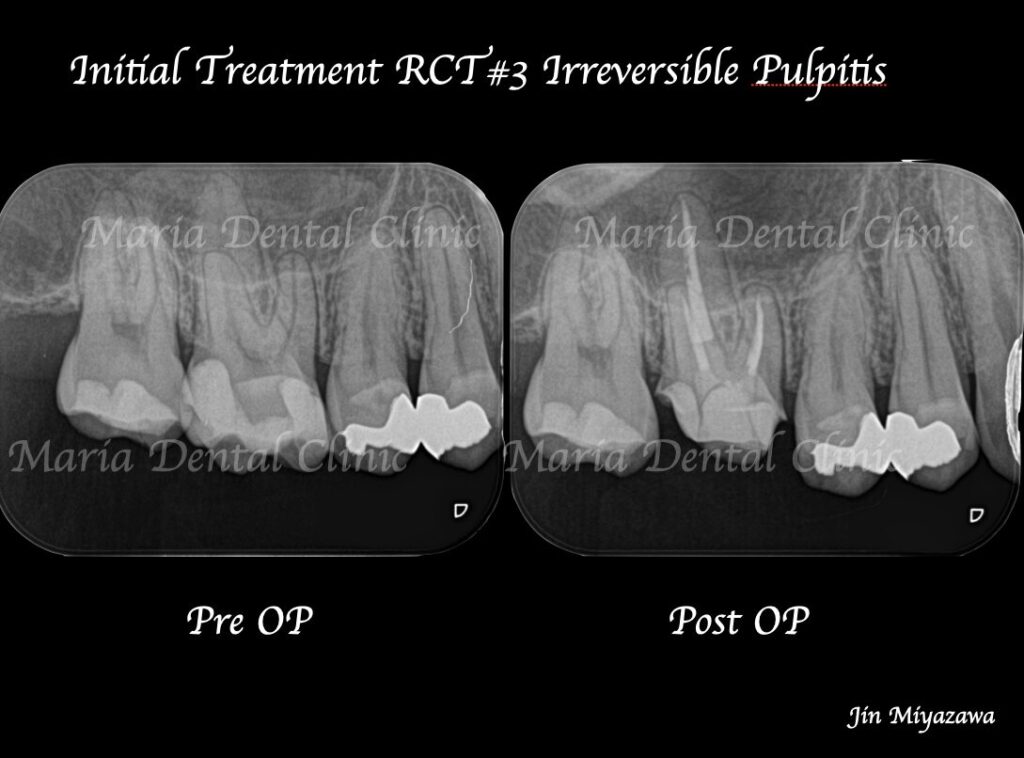

_術前術後の比較画像|目白マリア歯科-1024x758.jpg)

2回目の治療にて根管充填、支台築造処置まで終了しました。

2回目の治療開始時(1回目の治療から1週間経過後)には痛みは完全に消失していました。今後仮歯を製作し、問題がなければ最終補綴処置(被せもの)の製作に移行します。